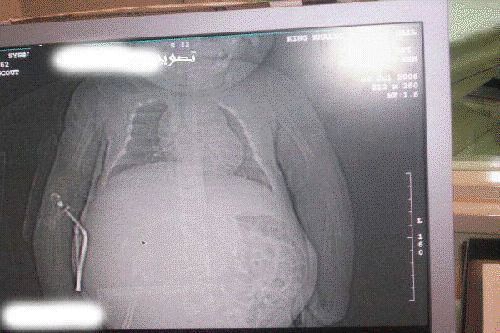

طفله تبلغ من العمر سنة واحدة وجدت حامل في المملكه العربية السعودية. ويقول الاطباء انها حالة فريدة في العالم!

ويقول التقرير : ان الأم كانت حاملا بجنينين ولكن احداهما نما داخل الآخر.